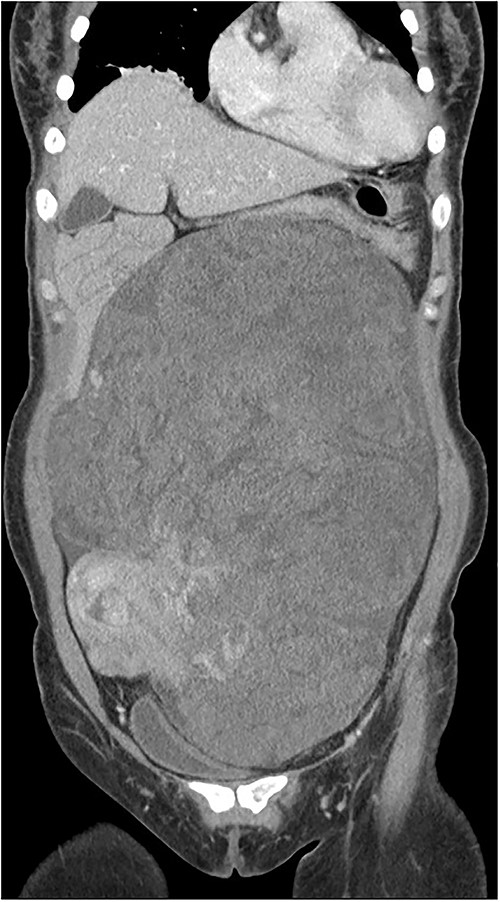

Computed tomography (CT) of the enhanced upper abdomen showed a well-defined, heterogeneous, focally enhanced soft tissue (30 × 20 × 9 cm) occupying the abdomen and pelvic cavity. The bowel and the uterus were displaced by the mass (Fig. 1). Magnetic resonance imaging of the pelvis showed that this mass was independent and not a lymph node mass but a type of retroperitoneal sarcoma. Positron-emission tomography–CT showed that a huge mass (32 × 23 × 12 cm) in the abdominopelvic cavity, with mostly heterogeneous mild 18F-FDG uptake.

During the surgical procedure, the general surgery team discovered a sizable, multilobulated, and hypervascular mass situated in the retroperitoneum. It occupied almost all parts of the abdominal cavity and was nearly in contact with the pelvic floor at the transverse colon level. The descending and sigmoid colon, rectum, uterus, and both ovaries were pushed to the right and attached firmly to the rear of the uterus. The mass was dissected gently from left lateral side of retroperitoneum to descending and sigmoid colon. Despite big size and thin wall, it was easily detached from colon and retroperitoneum. But it was found that the mass was firmly attached to rear of the uterus during dissection within pelvic cavity. The mass could not be removed with preserving the uterus (Fig. 2).